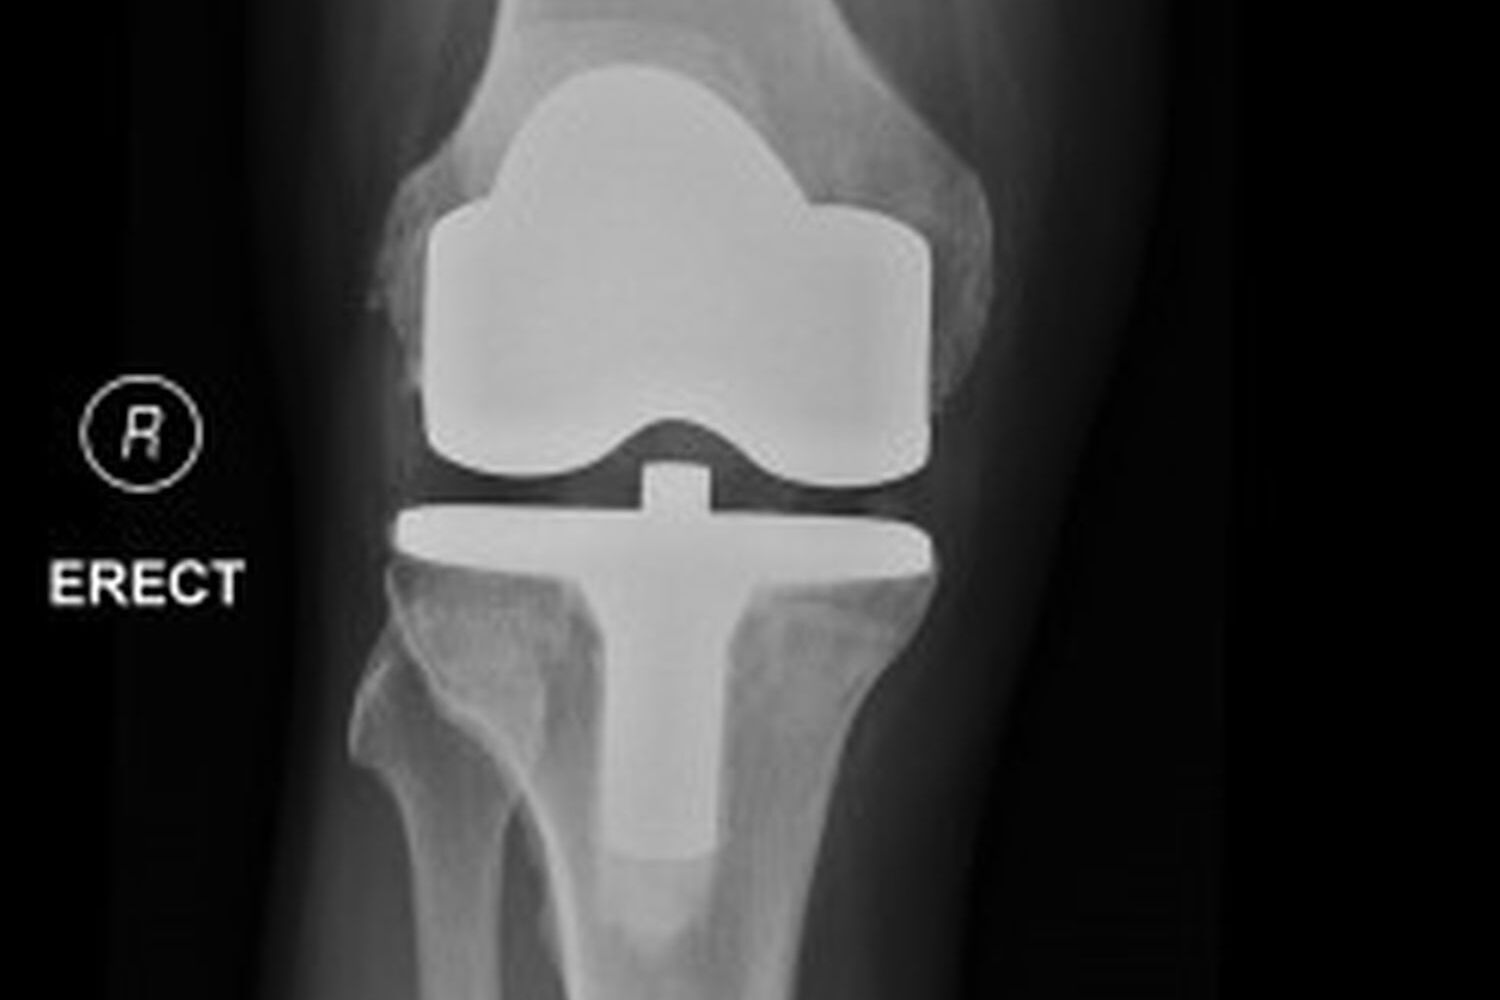

Knee

- Joint Replacement